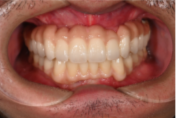

オールオン4の症例紹介①

Before

After

主訴

歯がぐらぐらして噛めない

治療内容

全ての歯を抜歯し、

上顎、下顎に対するインプラント治療を行った。

治療費

4,092,000円(税込)

治療期間

1日

通院回数

3回

※治療回数は1回

想定されたリスク

※最終的な歯が入るまでは仮歯となりました。

オールオン4は、4本のインプラントで片顎の人口歯を支える治療法です。重度の歯周病や総入れ歯の方に適しています。